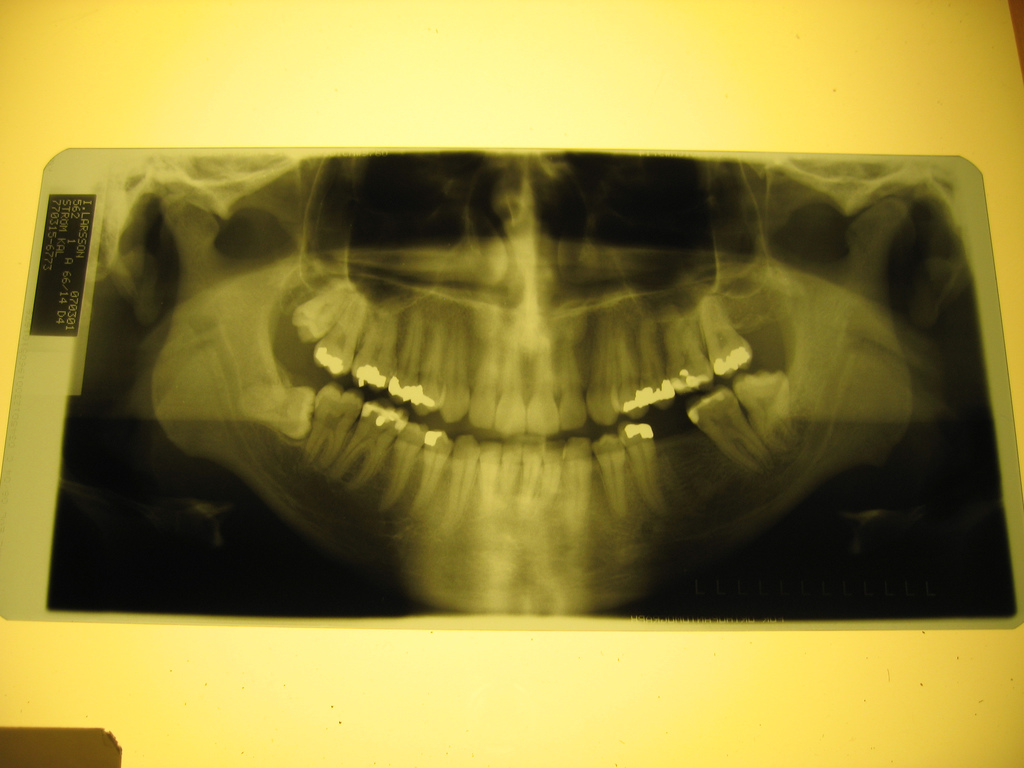

4. Åldersbestämning av immigranter Motion 2014/15:1127

Kent Ekeroth (SD) misstror att ensamkommande flyktingbarn är barn (under 18 år). Där för vill Ekeroth införa “röntgen av tänder, handleder men eventuellt även andra nya metoder som har ännu större tillförlitlighet”. Åldersbestämningen ska omfatta alla som “påstår sig vara under 18 år eller av andra påstås vara under 18 år, eller som av andra anledningar antas vara under 18 år”. De som vägrar att genomföra undersökningen ska få sin utredning avslagen och “personen i fråga ut- eller avvisas”.